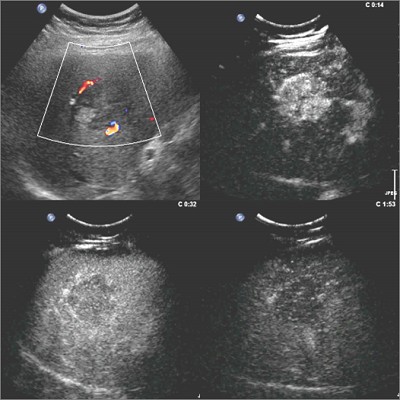

图2

图1和图2分别为两例肝脏占位性病变,仅凭二维和彩色多普勒超声无法定性,分别作了超声造影检查,根据病灶增强模式等超声造影特点,诊断出图1中的病灶为良性的血管瘤,临床上观察即可,而图2中的病灶为肝细胞癌,临床需要手术等治疗。